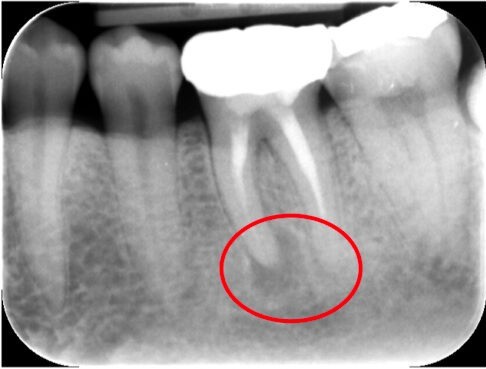

デンタルレントゲン

デンタルレントゲンは、特定の歯とその周辺の骨や組織をピンポイントで詳細に撮影できる装置です。虫歯の深さを調べたり、根の治療のあとに薬がしっかり根の先まで詰まっているかを確認したりと、日々の診療のさまざまな場面で活躍します。